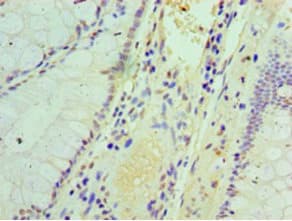

Rabbit Polyclonal IFIT3/P60 antibody. Suitable for IP, WB, IHC-P, ICC/IF and reacts with Human samples. Cited in 1 publication. Immunogen corresponding to Recombinant Full Length Protein corresponding to Human IFIT3.

Applications ICC/IF, IHC-P, IP, WB